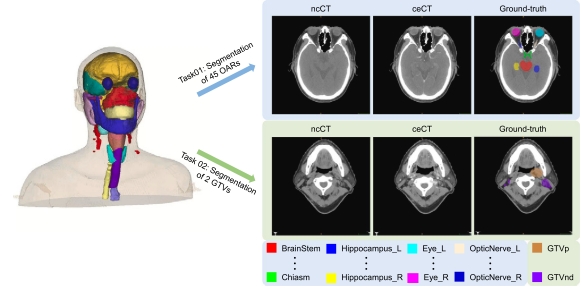

4,SegRap Dataset [Downlaod]

This isa large-scale benchmark for OAR and GTV segmentation with 400 Computed Tomography (CT) scans from 200 NPC patients, each with a pair of pre-aligned non-contrast and contrast-enhanced CT scans. It aimes to segment 45 OARs and 2 GTVs from the paired CT scans per patient. Reference:

Xiangde Luo, Jia Fu, ..., Shichuan Zhang, Wenjun Liao, Guotai Wang*, Shaoting Zhang* SegRap2023: A Benchmark of Organs-at-Risk and Gross Tumor Volume Segmentation for Radiotherapy Planning of Nasopharyngeal Carcinoma.Medical Image Analysis, 101,April (2025): 103447.